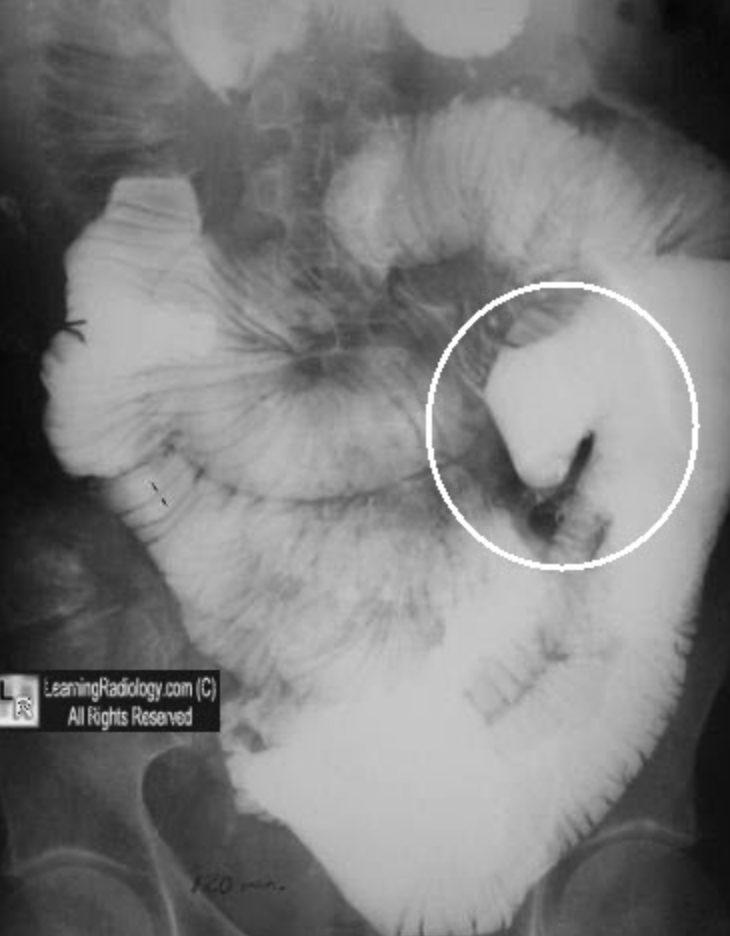

Moulage sign and ceoliac disease

Loss of jejunal folds/mucosa

The moulage sign is related to sprue, in particular coeliac disease. It occurs where there is a dilated jejunal loop with complete loss of jejunal folds 1. It is said to appear like a tube into which wax has been poured.